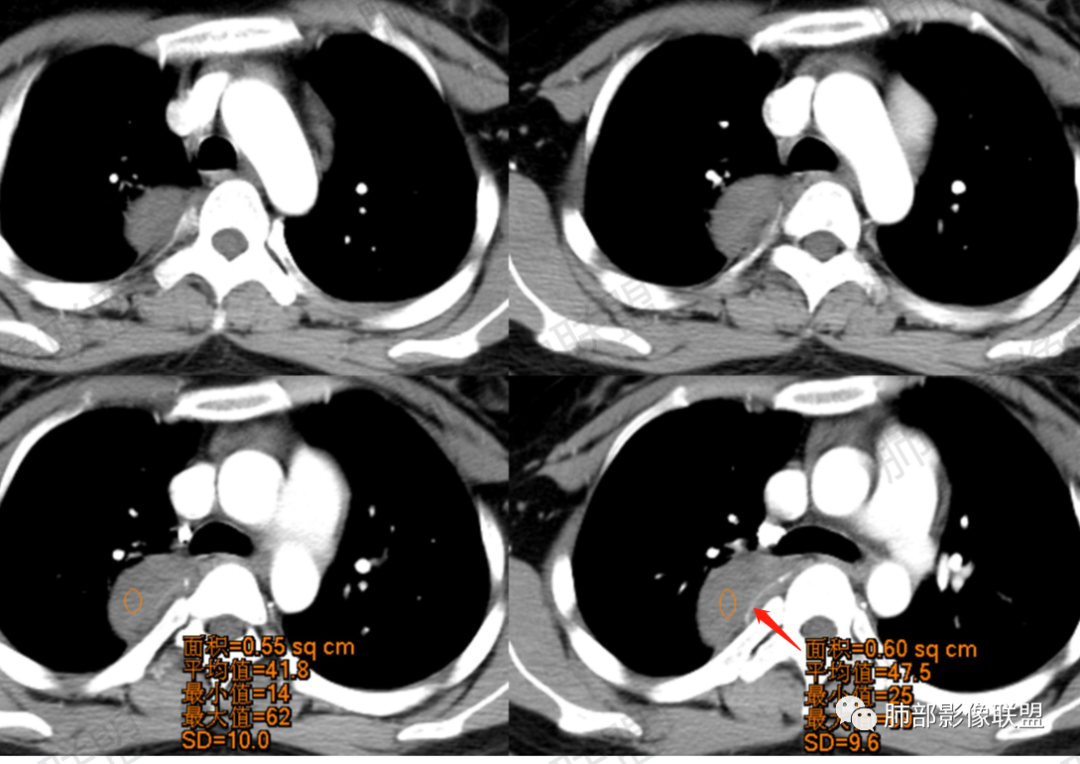

CT值平扫33HU,增强:45HU左右

定在轻度强化

5.轻度渐进性强化。

(3)增強:

后纵隔神经节细胞瘤常动脉期无明显強化、或轻度间隔、包膜或瘤体强化,延迟期可进一步斑片、结节状轻度或中度强化,强化程度进行增加,呈渐进性延迟强化,但強化程度一般为轻度到中度强化,究其原因可能是神经节细胞瘤瘤体内含有大量黏液基质和胶原纤维,使得细胞外间隙扩大,阻碍了对比剂的灌注,从而延缓了对比剂的积累,因此其动脉期多无明显强化或仅有轻度强化,延迟期呈渐进性轻度强化是后纵隔神经节细胞瘤强化特征。大部分病灶有轻度-中度强化,部分病灶无强化,这还可能与瘤组织内部间质血管含量多少相关,无强化病例瘤组织内部主要由胶质纤维和节细胞组成,间质血管较少,因此强化较低,而强化程度较高的病理可见较多的扩张、充血的毛细血管,引起较多的对比剂积蓄,因此强化相对明显。因此,神经节细胞瘤极少出现瘤组织早期强化,而多呈延长渐进性强化,增强扫描神经节细胞瘤内细胞成分可增强,黏液基质不强化。